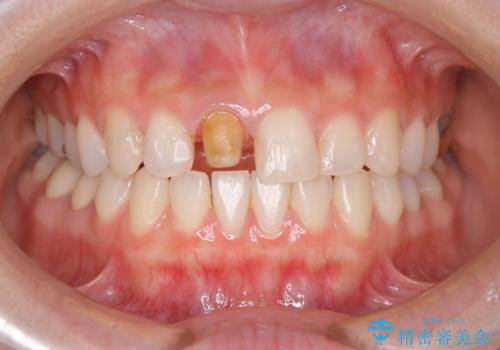

- 前歯一本だけ色が暗いことが気になりご相談にいらした患者様です。周辺の歯と色味をぴったり合わせることで自然な仕上がりになりました。

根管治療をした歯は神経のある歯と比較して強度が下がり、長期的に破折のリスクが高まると言われています。破折のリスクを軽減させるため、根管治療を行った歯に対しては歯冠をすべて覆うクラウンという被せ物にて補綴処置を行います。